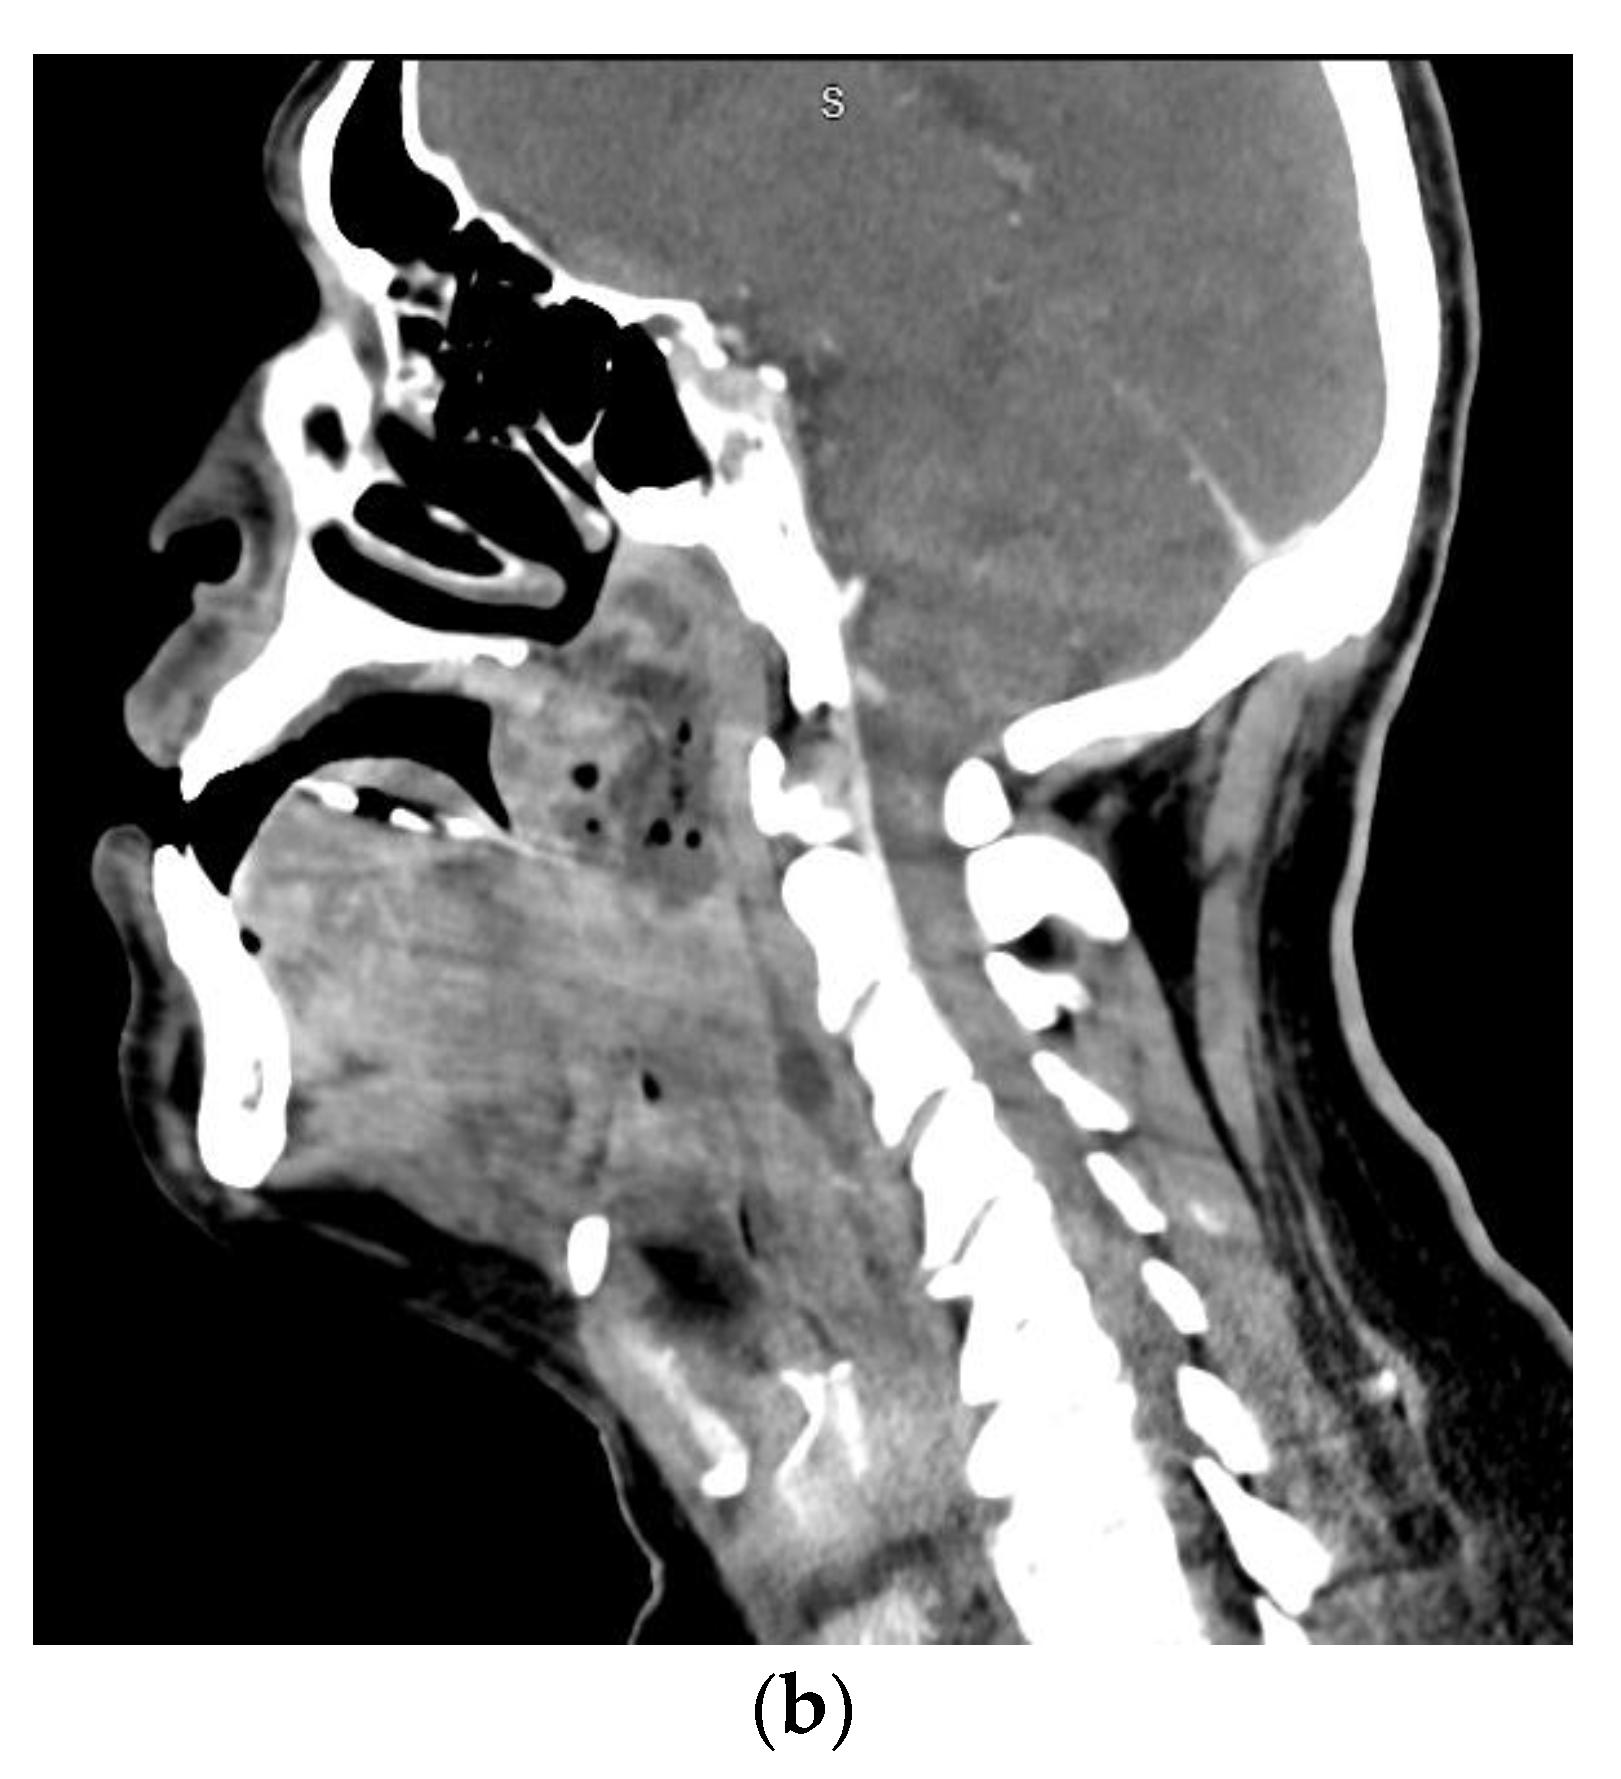

1.3. Descending Necrotizing Mediastinitis

1.4. Orbital Cellulitis, Abscess, and Septic Cavernous Sinus Thrombosis